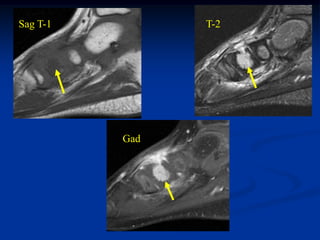

Case #1095

58 year female with

adamantinoma tibia

Sagittal T-1 MRI

Sagittal T-2 MRI